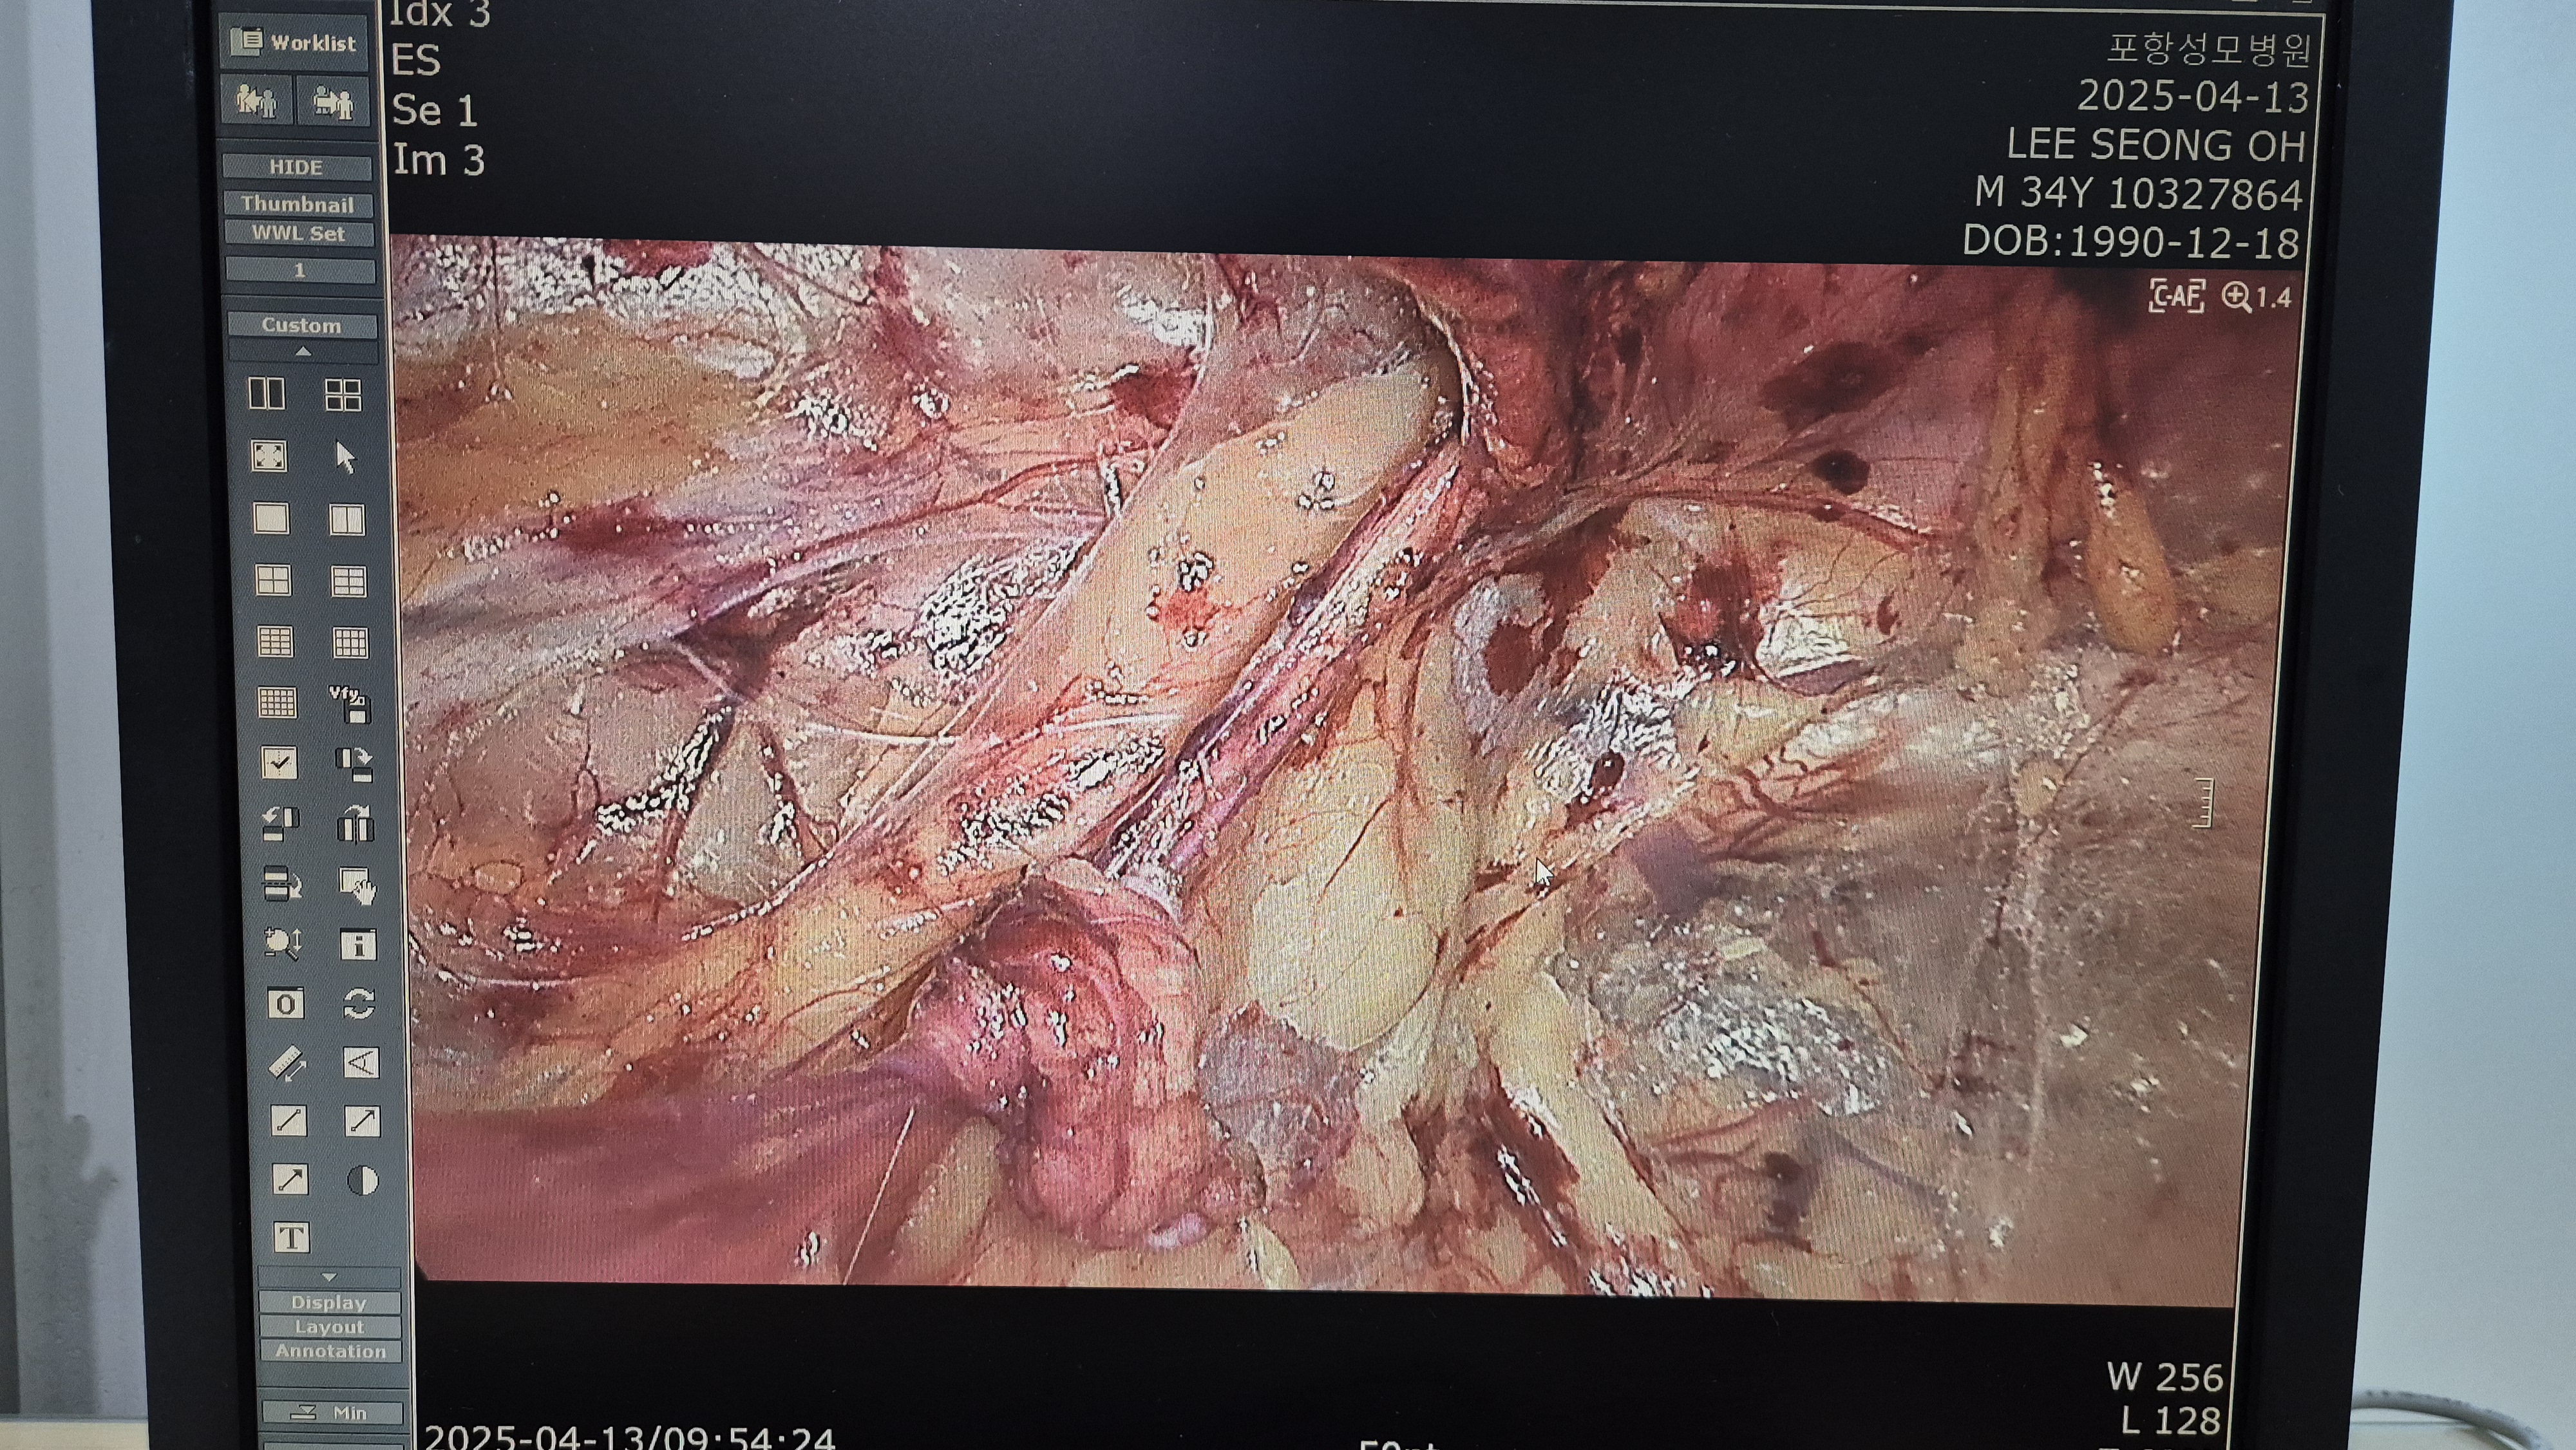

탈장 확인후.

박리.